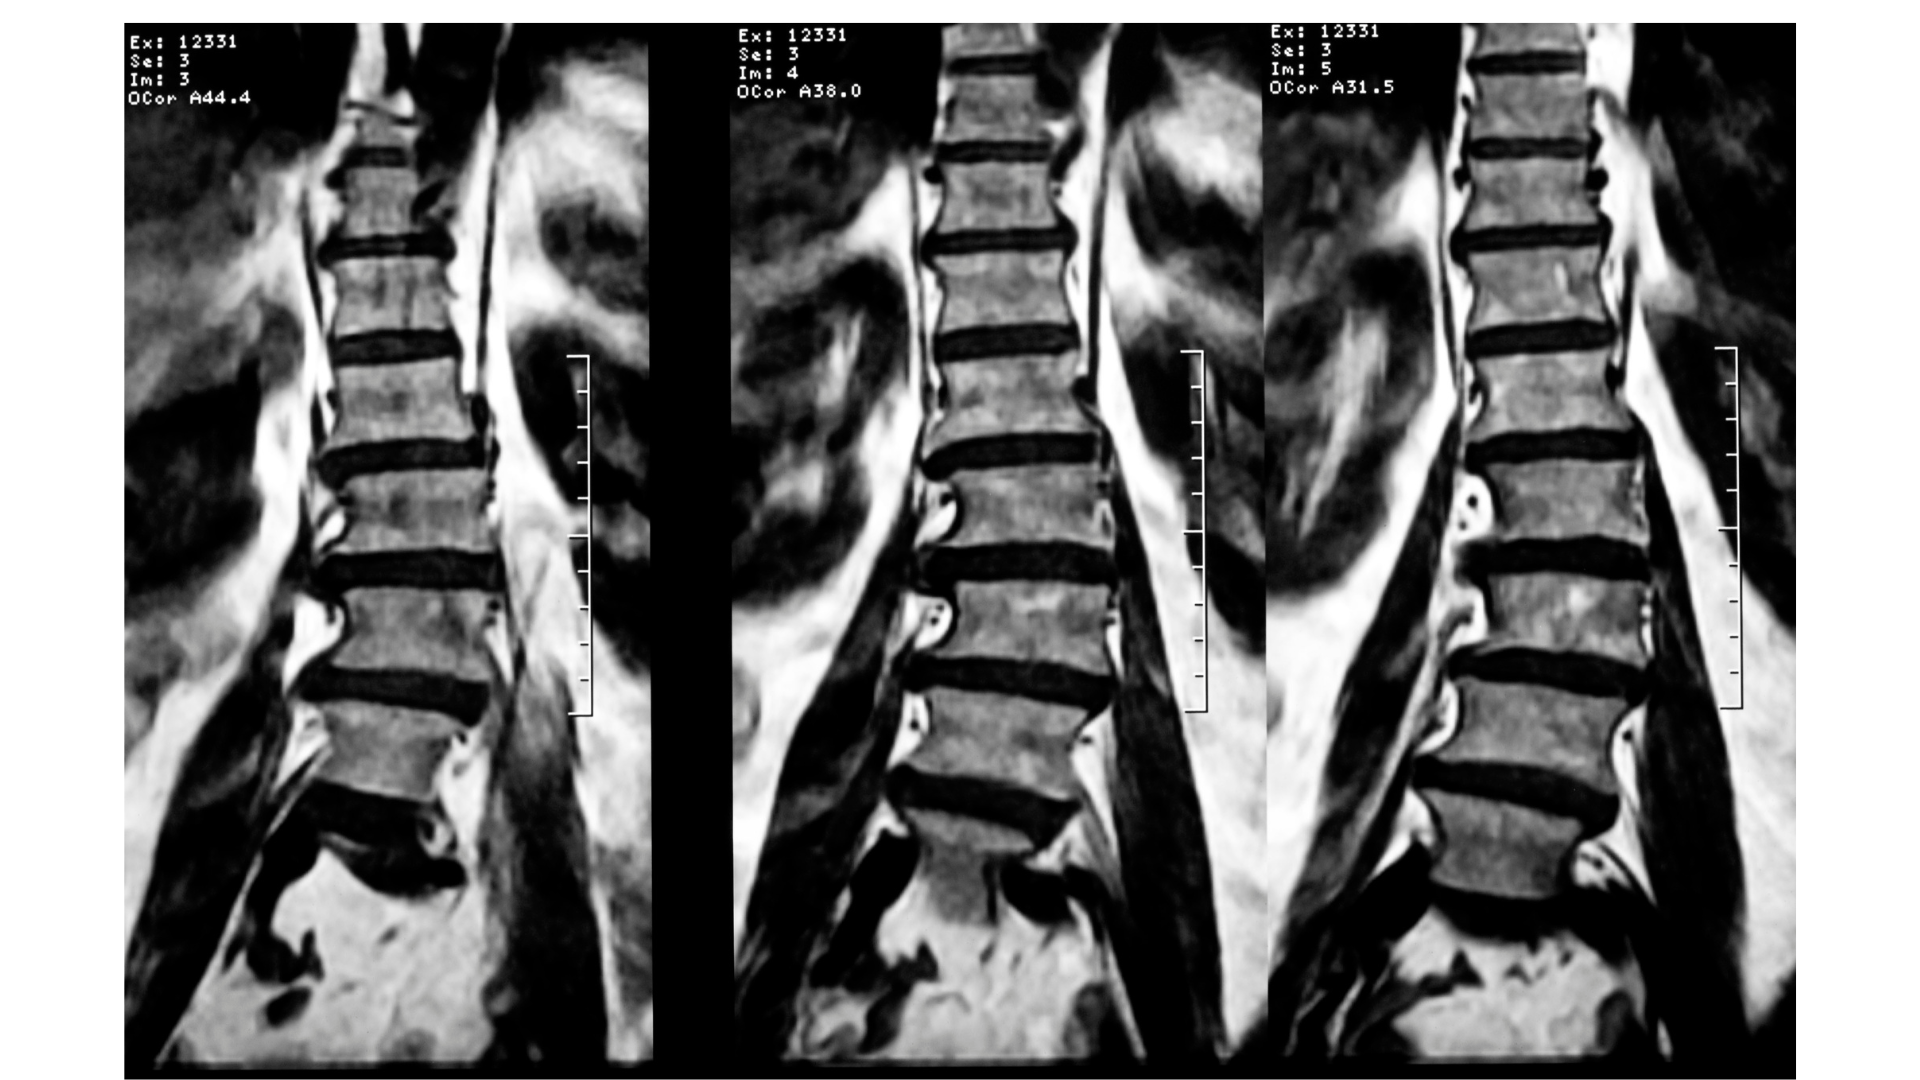

FISIOTERAPIA ESPECIALIZADA EM ESCOLIOSE

A Fisioterapia para escoliose é um tratamento personalizado, baseado em exercícios específicos com comprovação científica. Seguimos as diretrizes da Sociedade Internacional de Tratamento da Escoliose (SOSORT) e, através de uma avaliação individual, traçamos um plano de tratamento visando o equilíbrio e a estabilidade do corpo. Utilizamos técnicas modernas e atuais, com o objetivo de não apenas tratar a condição, mas também melhorar a qualidade de vida do paciente, permitindo maior facilidade nos movimentos e uma postura mais correta. Entre os principais métodos utilizados destacam-se: